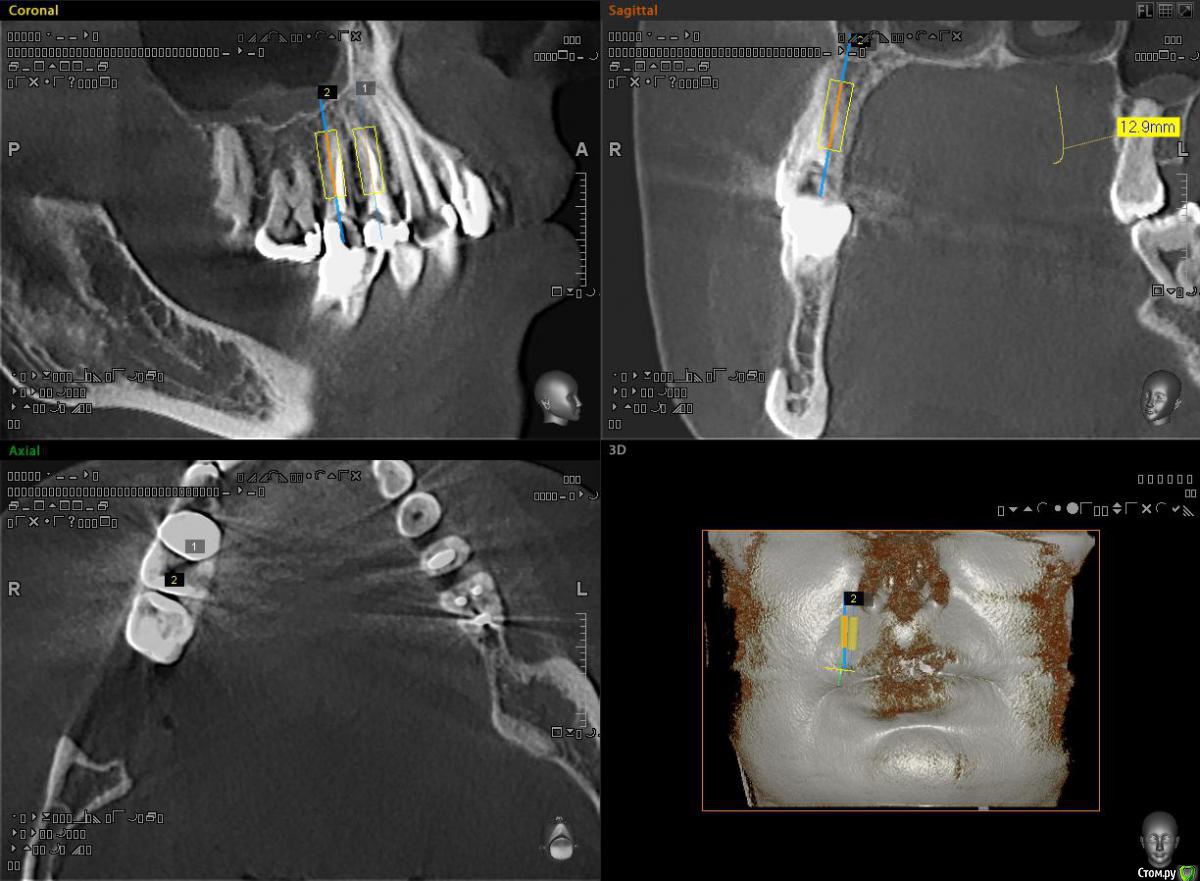

alekszander Опубликовано 3 ноября, 2015 Поделиться Опубликовано 3 ноября, 2015 Всем доброго времени суток! Снова нужна помощь коллеги.Пациентка направлена на ортопедию от врача терапевта. Ситуация - тотальный дефект зубы 1.5.1.4. Сохранить можно только на ЛКШВ(чего я не люблю .Согласна на имплантаты, НО - дефицит места как по высоте(относительно для одомоментной), так и по апроксимальным контактам. Имлантаты виртуально выставил 3.3х10. Длинее в 1.4 не поставить, апекс клыка мешает. Зуб 1.5 можно и 12мм. Смущает места между имплантатами и место до корней зубов. Между винтами ~2.5 мм. до корней ~1.5-2 мм. Что посоветуете? как сами поступаете в таких случаях? Ссылка на комментарий

diesel87 Опубликовано 3 ноября, 2015 Поделиться Опубликовано 3 ноября, 2015 Вы не совсем понимаете работа с просмотрщиком кт, не по тем срезам судите. Если одномоментно, то оба винта можно 3.8-4.3 брать и длина 11,5-13 с бикортикальной фиксацией. Хирург вы? Ссылка на комментарий

Доктор Добрых Дел Опубликовано 3 ноября, 2015 Поделиться Опубликовано 3 ноября, 2015 По-моему места вагон! Срезы поменяйте и все станет на свои места Ссылка на комментарий

alekszander Опубликовано 4 ноября, 2015 Автор Поделиться Опубликовано 4 ноября, 2015 Спасибо за советы.1. Для Diesel87(простите имени не знаю). Да я хирург. Здесь все срезы выставить не могу, но максимум там проходят 3.3 чтобы потом нормально запротезировать. Бикортикально не хочу, т.к. в наличии только мис и адин, а у них агресивный апекс, есть риск. А насчет длины согласен можно и длинее. 2. Карен, Александр. Вот и у меня сомнения. Но там нужна реэндодонтия,ЛКШВ,клин. удлинение, и только потом постоянные коронки. По срокам и цене получится чуть дешевле имплантации.Вот и задумываюсь что лучше. Ссылка на комментарий